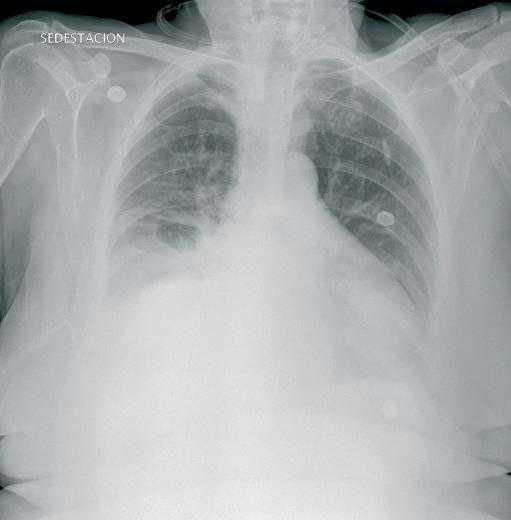

She is a 76-year-old woman, with stage 5 chronic kidney disease with interstitial nephropathy. Over the past three years, she has been receiving continuous ambulatory peritoneal dialysis, with three daily 2,000ml refills. Over this period, she has not suffered peritonitis nor has she undergone surgery. In a routine check-up, a small non-incarcerated umbilical hernia and an abdominal hernia were detected, the latter measuring approximately 6cm in diameter in the left paramedian line and confirmed by CT scan and ultrasound. The peritoneal dialysis was not affected by these anatomical alterations, so after surgical evaluation a conservative stance was maintained, modifying the dialysis rate to four daily 1,500ml refills. She returned to the hospital six months later with cloudy fluid, fever and mild abdominal pain, with a 5 hour evolution. In the days before, she had suffered mild diarrhoea. The peritoneal effluent cell count was 4,570cells/ml (98% PMN). Diagnosed with bacterial peritonitis in peritoneal dialysis, she was admitted and put on intraperitoneal antibiotic therapy, following our centre’s protocol: vancomycin, ampicillin and tobramycin. On the following day, the fluid was still cloudy and cell count was 9,850cells/ml (94% PMN); the peritoneal dialysis balance showed a gain of 1,200ml and the abdominal pain persisted. Thirty-six hours after admittance, she suffered sudden dyspnoea. The patient presented a generally poor state: she was pale, sweaty, tachypneic and had difficulty breathing. Oxygen saturation was 90%. The respiratory auscultation displayed a reduced breath sounds in the right hemithorax. The chest X-ray displays a moderate right pleural effusion (Figure 1). A short hypertonic refill is administered with no improvement. Due to paroxysmal breathing difficulty and the X-ray results, thoracocentesis was performed, which drained 2,000ml. The pleural fluid was a glucose concentration of 269mg/dl, much higher than the plasmatic concentration (110mg/dl), which confirmed hydrothorax. Improvement was significant after the pleural tap. The peritoneal dialysis was suspended and on receiving the peritoneal fluid culture, positive for Bacteroidesfragilis, intravenous antibiotic therapy was started with meropenem and metronidazole. The abdominal CT scan ruled out perforation and other intra-abdominal pathologies. After two weeks of treatment, she was discharged and is currently on regular haemodialysis.

Figure 1. Hydrothorax